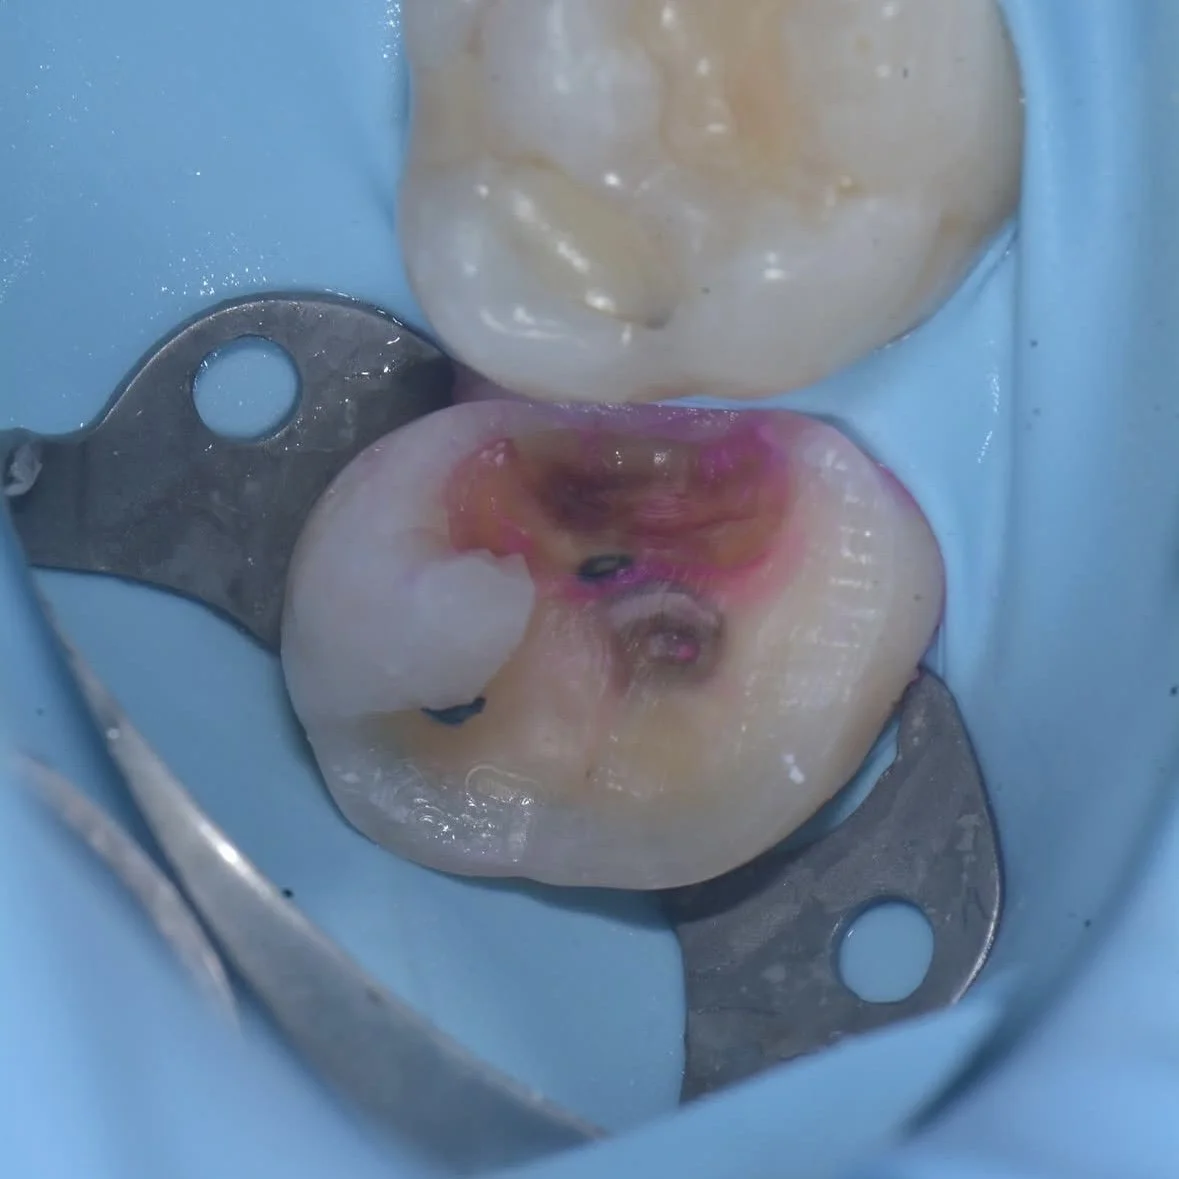

Here are two examples of caries removal endpoints (CRE) in this case by Dr. Davey Alleman, DMD. Complete caries removal was possible on the left tooth, while the right tooth required partial caries removal to preserve the pulp vitality.

This case by Dr. Davey Alleman, DMD shows the process of removing caries around the pulp to create a caries-free peripheral seal zone.